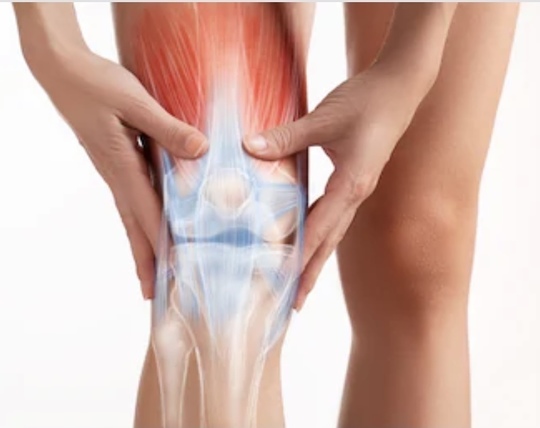

膝関節には、3つの動きがあります。

それは、『ころがり』『すべり』『回旋』の

3つの動きになります。

膝が痛い方は特に、この『回旋』の動きがなくなる事が多くみられますが、そのほかにも『ころがり』『すべり』も制限されることは多くあります。

特に、膝の状態が悪くなればなるほど3つの関節の動きが制限されます。

膝の関節のうごきである『ころがり』『すべり』『回旋』のうごきを作る事がポイントになってきます。

この3つの『ころがり』『すべり』『回旋』の動きを作れば膝の機能は修正されますが、この機能を修正せずに筋トレをするといつまでも膝は痛いままになります。